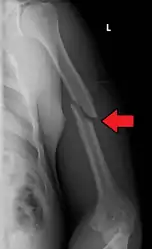

A transverse fracture of the humerus shaft

A spiral fracture of the distal one-third of the humerus shaft